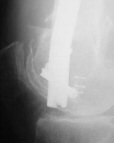

Attached are few examples from our Hospital:

A. Difficult reductions, even in retrograde nailing (my preference, easier control of "small" distal fragment) and it is much, much harder to do it anterograde (Alex, do you have one good case in your collection of anterograde nailing in very distal fractures - as you have suggested that I

should have done it in my previously posted case?

Malpositioning is much too common (recurvatum, varus - valgus).

B. Fixation loosening: distal cutting of the nail, non-unions do happen (cases attached).

Locking Plating has more distal screws than any nail, fixed angles and provides much better fixation, especially in osteoporotic bone.